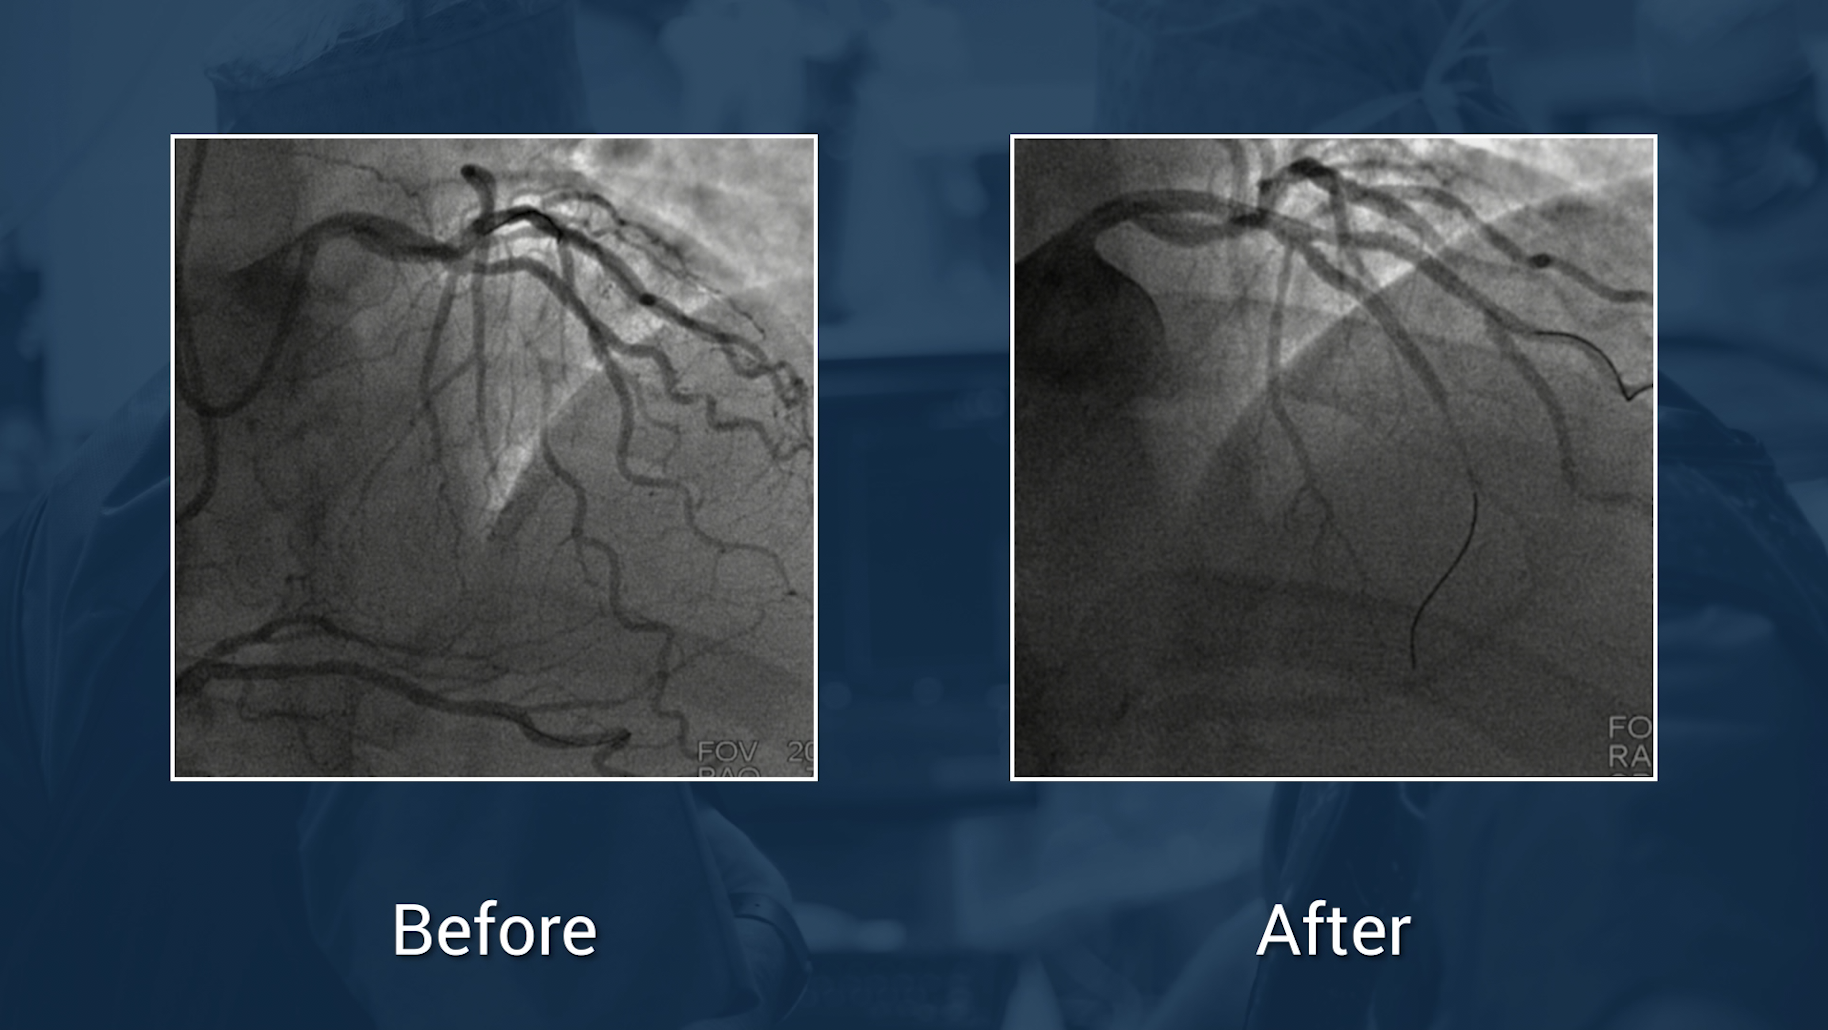

LAD diagonal bifurcation treatment in the simplest way

Dr Alexandre Avran, Dr Robert Gil & Dr Nicolas Lhoest

Cardiology

Coronary

Pci

Case in the box

Treatment of Ostial LAD lesion

Dr Khalifé & Dr Lefèvre

A complex biradial LAD CTO

Dr Valla & Dr Lefèvre

Rotablator in a highly calcified LAD lesion

Retrograde approach in a CTO of a multistented RCA

Dr Khalifé, Dr Lefèvre & Dr Marwan

How to approach ostial RCA CTO: a case based strategy ?

Case of the month: May 2020

Cto

ML CTO 2021 - Dr. Knaapen & Dr. Nap

Double CTO recanalizatiob of RCA and CX

Live Case